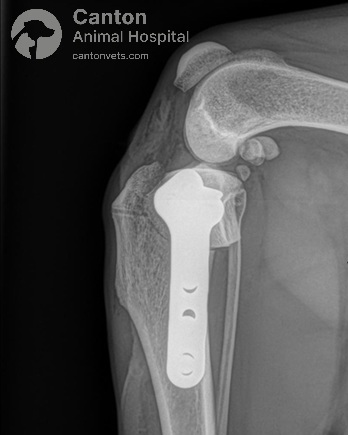

The proximal tibia (top of the shinbone) is carefully cut and rotated to change the slope of the tibial plateau.

A specialized bone plate is used to stabilize the osteotomy, ensuring proper healing.

By reducing the tibial plateau angle, the cranial tibial thrust is neutralized, allowing the dog to bear weight without abnormal joint movement.

TPLO Implants and Fixation

Different types of bone plates and screws are used to stabilize the tibia post-surgery. At our hospital, we use the TPLO Locking System (Plate and Screws) from DePuy Synthes Vet, which ensures maximum strength and stability during healing.